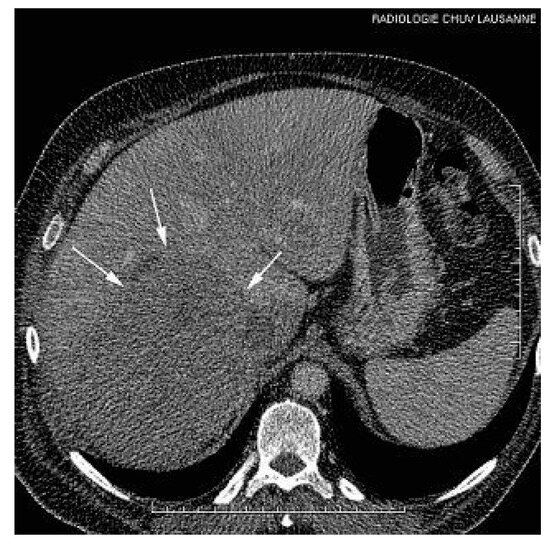

This report describes a case of involvement of inferior vena cava and the right atrium (RA) by a hepatocellular carcinoma (HCC), incidentally discovered during a transthoracic echocardiography in a patient with segmental left ventricular dysfunction,...